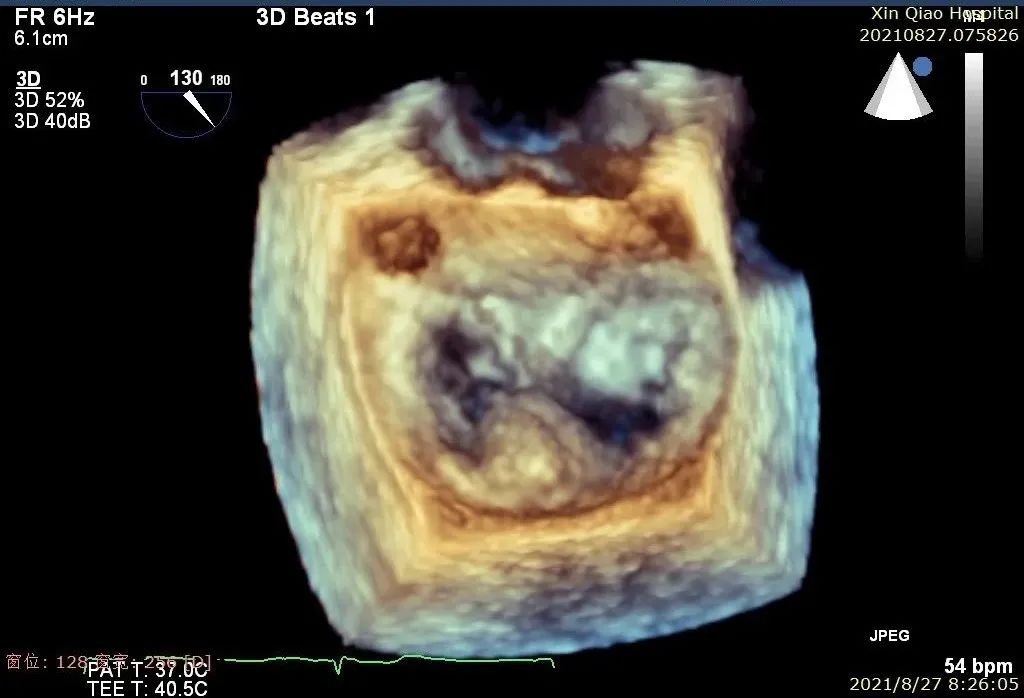

患者术后B超图

术后即刻,患者反流显著减小,二尖瓣反流从4+减少到1+以下,左房压下降,血流动力学改善明显,手术取得了圆满成功。